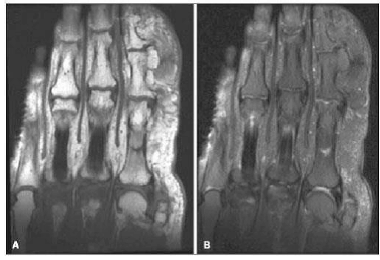

As figuras a seguir mostram cortes coronais da mão direita em ressonância magnética, os quais são ponderados: em T1, sem saturação de gordura (figura A) e, em T2, com saturação de gordura (figura B).